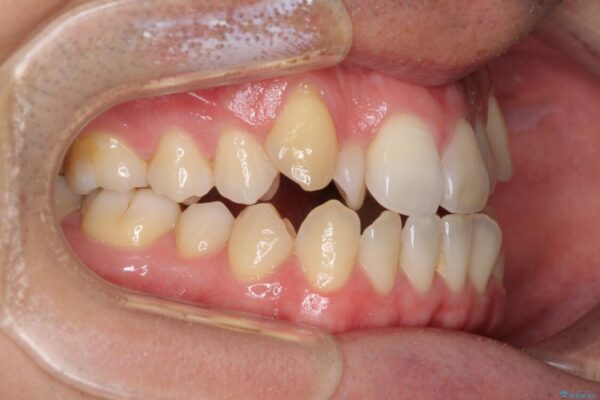

治療前

• 左右の八重歯が気になる ワイヤー装置での咬み合わせ改善 治療前画像